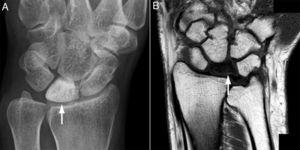

A partir de la revisión retrospectiva de 115 casos de la consulta monográfica de ES de nuestro centro, se identificaron 4 pacientes que desarrollaron ON del semilunar (tabla 1). La edad media fue de 59,5±12,6 años, siendo todas mujeres. Dos de los casos correspondieron a ES cutánea limitada y 2 a ES cutánea difusa. Ningún caso presentó anticuerpos antifosfolípidos ni tuvo eventos trombóticos previos. La media de evolución de la enfermedad fue de 13,5 años (rango: 7-17 años). Una paciente era exfumadora y ninguna tenía hábito enólico. Cabe destacar que todas tuvieron compromiso vascular (fenómeno de Raynaud [FR] grave con úlceras digitales, tratado con antagonistas de endotelina y perfusión de prostaglandinas intravenosas, y un caso presentó isquemia digital crítica); todas tuvieron calcinosis en extremidades superiores, además de compromiso articular (2), pulmonar (2) y digestivo (4). Todas habían recibido terapia prolongada con glucocorticoides a dosis bajas (5-10mg/día de prednisona) antes del diagnóstico de ON. La presentación de ON del semilunar fue unilateral en 3 casos y bilateral en 1, requiriéndose manejo quirúrgico en una paciente (carpectomía proximal). Las pacientes referían dolor de predominio mecánico, de inicio insidioso y curso progresivo, de varios meses de evolución, en la articulación afectada. El diagnóstico se confirmó mediante radiografía simple, gammagrafía ósea y/o resonancia magnética (RM) (fig. 1). En un caso se evidenció en la RM sinovitis extensa en el carpo y en otro colapso del semilunar con fragmento desplazado e importante edema óseo.